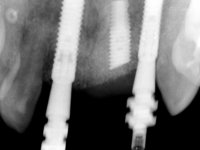

Paciente do sexo feminino, com 30 anos de idade, não fumadora. A paciente surge na consulta após tratamento ortodôntico e colocação de um implante no local do dente 2.1. Apresentava os dentes 3.7, 3.6 e 4.7 com tratamento endodôntico e os dentes 1.5, 2.5, 2.6 e 4.5 com restaurações extensas. Apresentava um periodonto fino e mostrava uma higiene oral satisfatória. Após exposição cirúrgica do implante este mostrou-se posicionado de forma inadequada. A reabilitação protética do implante mostrou-se impossível adotando critérios estéticos aceitáveis. A paciente durante 6 anos andou com uma coroa provisória de acrílico sobre um coto aparafusado como solução de recurso já que não aceitou a proposta de remover o implante. Após este tempo surge na consulta com um abcesso no dente 1.1. Analisada a situação constatou-se que os dentes 1.1 e 2.2 tinham extração indicada e o implante deveria ser removido ou submergido.

Na fase inicial, foi proposto à paciente fazer a exposição cirúrgica do implante e após avaliação clínica tomar decisões protéticas. Colocado o parafuso de cicatrização e feita a cicatrização dos tecidos moles, foi constatada uma posição inadequada do implante. Perante o dramatismo da situação foi proposto à paciente a remoção do implante e após regeneração tecidular colocar um novo implante. Esta proposta foi recusada pela paciente e foi sugerido por esta a reabilitação provisória do implante. Nesse sentido foi então feita nova proposta, desta feita, reabilitando o implante. Foi sugerido a confeção de um coto aparafusado e sobre este a colocação de uma coroa de acrílico com componente coronário e gengival. Passados 6 anos com o tratamento provisório a paciente surge na consulta com um abcesso no dente 1.1. Feita a análise clínica e imagiológica decidiu-se extrair os dentes 1.1 e 2.2, submergir o implante, colocar dois implantes no local dos 1.1 e 2.2 e fazer regeneração tecidular adequada. A temporização seria feita com uma ponte provisória de 3 elementos aderida com uma rede aos dentes vizinhos. Após osteointegração seria reabilitada definitivamente com uma ponte de 3 elementos, com infraestrutura de Zr revestida a cerâmica.

A exposição cirúrgica do implante e a colocação do parafuso de cicatrização mostrou-se uma surpresa negativa no que diz respeito à sua posição. Rejeitada a proposta de remoção do implante, avançamos para a sua reabilitação provisória. Foi feita a impressão por técnica de moldeira aberta e em laboratório foi confecionado um coto aparafusado com componente gengival e coronário e uma coroa em acrílico também com estes dois componentes. A coroa provisória foi colocada em boca até ser tomada uma decisão definitiva. Passaram 6 anos até que a paciente retorna à consulta com um abcesso no dente 1.1. Tomada a decisão de extrair os dentes 1.1 e 2.2 foi feita uma impressão para confecionar uma ponte provisória de 3 elementos com uma rede para ser aderida aos dentes adjacentes. A cirurgia foi planificada e realizada, colocando-se os dois implantes no local do 1.1 e 2.2 e o implante no local do 2.1 foi cortado com o objetivo de o submergir, simultaneamente foi feita a regeneração tecidular adequada (Trabalho Cirúrgico realizado por Dr. Manuel Neves). Durante a osteointegração a paciente utilizou a ponte provisória fixa. Foi realizada primeira impressão para a confeção de uma ponte provisória aparafusada em Zr que trabalhou durante 12 semanas os tecidos moles. A impressão definitiva foi feita com a individualização dos transferes. A reabilitação definitiva foi feita com cotos ceramizados e com uma ponte de infraestrutura em Zr revestida por cerâmica. Em virtude da inclinação do implante colocado no local do dente 1.1 a ponte exigiu fixação cimentada.